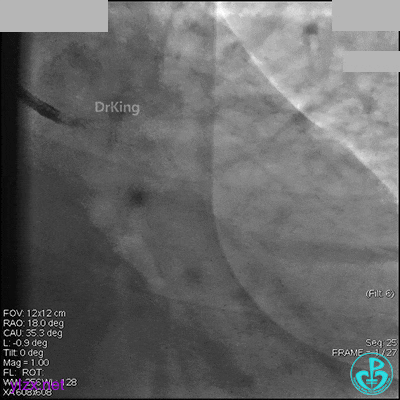

AL 1.0指引导管到位,简单短时尝试导丝不能顺利通过前降支或回旋支病变。改变策略处理右冠脉病变,计划植入2枚支架。AL指引导管到位,Sion blue导丝到达右冠脉远端。导丝通过后1.5mm及2.5mm球囊14~16atm充分扩张中段病变。

右冠脉中段充分扩张后欲植入3.5×38mm支架时,支架难以通过中远段扭曲处,且指引导管、导丝弹出飞扬。反复尝试导丝重新到达右冠脉远端时通过不顺利,局部造影剂滞留,远端血流接近3级。